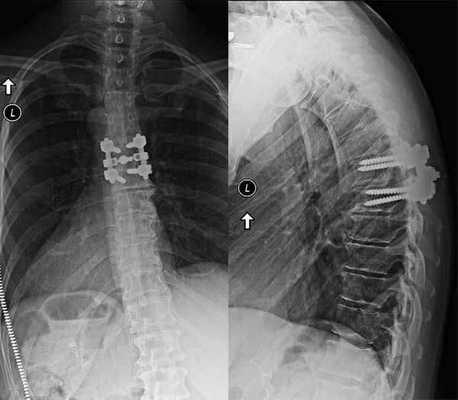

Поэтому в большинстве случаев спондилодез комбинируют с другими хирургическими манипуляциями на позвоночнике. При тяжелом спондилоартрозе пациентам выполняют фасетэктомию, при наличии спаек в области спинномозговых корешков - менингорадикулолиз, при сдавлении спинного мозга - декомпрессию дурального мешка. Вместе с этим всем больным удаляют МПД и заменяют их специальными кейджами. Такой подход позволяет устранить причину болей в спине и предупредить их появление в будущем.

Спондилодез относится к группе декомпрессивно-стабилизирующих операций. Все они направлены на освобождение сдавленных невральных структур, удаление разрушенных межпозвонковых суставов и дисков, стабилизацию ПДС.

Для более прочной иммобилизации ПДС многие хирурги выполняют межтеловой спондилодез вместе с транспедикулярной фиксацией. Суть последней заключается в применении специальных конструкций, которыми дополнительно скрепляют тела позвонков.